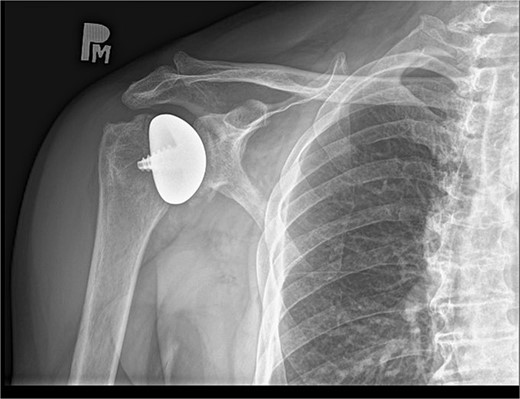

The peri and postoperative period passed without any complications. On day one after surgery, an X-ray image was taken (Fig. 9). The patient in good general and local condition was discharged from the hospital with a set of recommendations for rehabilitation. A sling was used to relieve the operated limb.

As a result, almost the full range of motion with a significant improvement in muscle strength of the right shoulder joint was achieved without any relevant pain reported by the patient. The results were confirmed by another right shoulder X-ray image (Fig. 10). The patient has been instructed to resume his pre-injury regular activities, including lifting heavy objects.